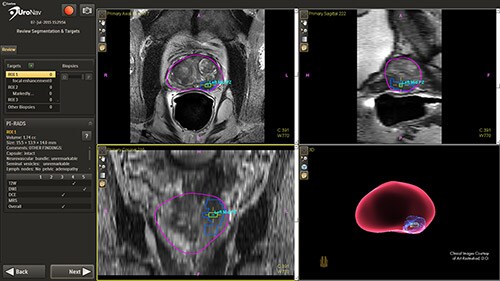

UroNav is an image-guided stereotactic biopsy system used to detect prostate cancer within patients as an alternative to current blind or blind systematic biopsies. It uses multi- parametric magnetic resonance (mpMR) imaging, fused with live ultrasound (US) guidance in conjunction with electromagnetic (EM) tracking to plan, guide, and document prostate biopsies. UroNav simultaneously displays registered MR and ultrasound images and the projected needle path relative to the suspicious target lesion during the biopsy procedure and guides the urologist in real-time.

This novel approach has the ability to improve the sensitivity and specificity of prostate biopsies. This results in a reduced incidence rate of false negative biopsy results. Conventional biopsy or “blind” procedures have a far lower cancer detection rate, which affects patient outcomes by delaying diagnosis, treatment intervention, and limiting treatment options. By enabling earlier diagnosis, UroNav allows a broader array of treatment options to be considered by the clinician, less complications for the patient, and a more cost-effective resolution for the care provider. From set up to post-biopsy review, UroNav guides you through its intuitive workflow. After a quick initialization of the navigation system (upper image), UroNav creates a 3D ultrasound volume from a standard 2D scan of the prostate (lower image).